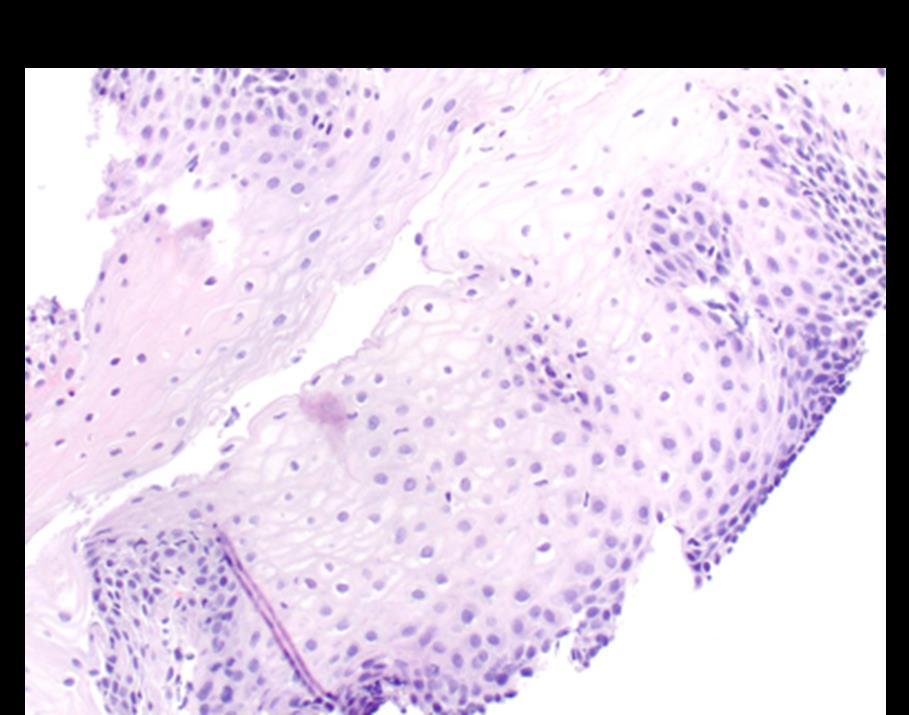

Dupilumab Improves Histologic Manifestations of Eosinophilic Esophagitis in a Real World Cohort of Pediatric Patients

Presenting Authors: Jing Marrero, MD, MPH, Emanuela Pinci, BS

Jing Marrero, MD, MPH, Emanuela Pinci, BS, Jeffrey S. Hyams, MD, Michael Brimacombe, PhD, Fabiola Balarezo, MD